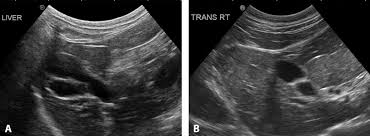

Disorders Of The Liver And Gallbladder In Dogs Dog Owners Veterinary Manual from www.msdvetmanual.com How common are liver tumors in cats and dogs? Removing the tumor and any associated cancerous cells is the best and most successful method of treating liver and spleen cancer. One defining feature of cancer is the rapid creation of abnormal cells that grow beyond their usual boundaries, and which can then invade adjoining parts of. The hope is that many cases of cats who live entirely indoors and who never have contact with other animals are rarely exposed to the virus and do. However, research has shown that they may be at more serious risk if you smoke, they eat. These diseases include diabetes mellitus and hyperthyroidism. Sometimes the lumps are the result of injury , other times they are benign growths. What is it and how is it diagnosed?

Hepatic Lipidosis In Cats Fatty Liver Syndrome In Cats Vca Animal Hospital from vcahospitals.com How common are liver tumors in cats and dogs? Cancer in cats is unfortunately considered relatively common and more prevalent than ever before. Cancer in cats can be very difficult to find, as cats can easily hide their pain. Can household chemicals or other common items, like bug sprays, cause cancer in cats because they walk through the residues and then lick their feet? These diseases include diabetes mellitus and hyperthyroidism. The diet usually recommended for cats with liver disease is typically easy to digest and high in calories. Nafld can cause cirrhosis (scarring of the liver) and liver failure. Some liver disorders require modifications of fat or several diseases involving endocrine glands can cause liver problems in cats.

Liver Disease In Cats Symptoms Causes Diagnosis Treatment Recovery Management Cost from images.wagwalkingweb.com Fortunately, although liver cancer in cats is a serious condition, it isn't always a death sentence. Cats and dogs develop cancer at nearly the same rate as humans. While a diagnosis of cancer is never good, early detection and treatment of cancer in cats can be remarkably successful. In fact, cancer is currently the leading cause of death in dogs (excluding euthanasia by humans for various reasons). Liver tumors in cats tend to be less aggressive than in dogs. Here are some things you can be on the in most cases, the cancer is found before they have any severe symptoms. Horn cysts they arise from. It is a leading cause of death in elderly cats.